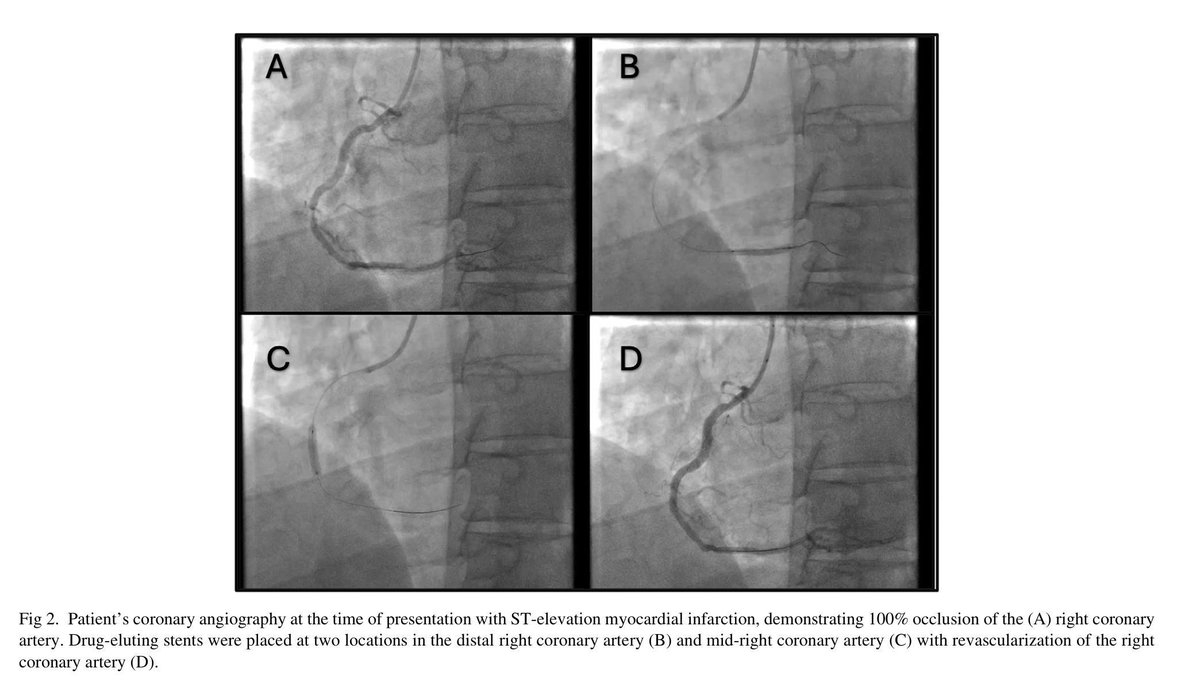

Stent Clot During Heart Surgery: A Close Call​​ ❗🩺 47yo man with heart attack got stent → needed urgent bypass 9 days later. Stopped blood thinner 2h before surgery → ​​clot formed in stent​​ during operation. #HeartSurgery #ClotRisk #QuickThinking jcvaonline.com/article/S1053-…

47yo man with heart attack got stent → needed urgent bypass 9 days later.

Stopped blood thinner 2h before surgery → ​​clot formed in stent​​ during operation.